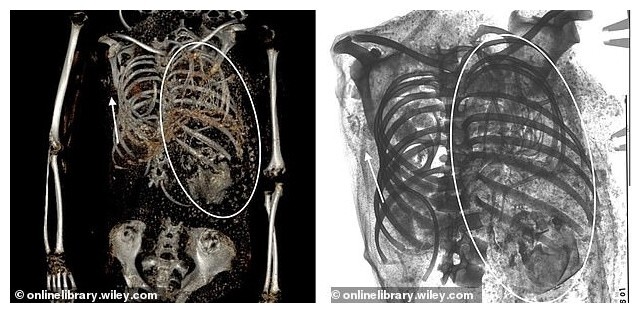

Researchers at George Washington University performed a CT scan of the body, finding a baby's head stuck in the birth canal and another fetus somehow displaced into the chest cavity.

A CT scan revealed a baby in the upper left side of the mummy's chest cavity, showing long bones, ribs, neural arches, a skull and five arm bones. The available records only spoke of the first twin and made no mention of the second fetus. It was only now that they were able to discover it. Scientists were able to determine the age of death of children - 36-40 prenatal weeks. This proves that they were twins.

“The detection of the fetal head at the pelvic inlet strongly suggests that labor is delayed,” the study says. “Probably the reason for the delay in labor was the breech presentation of the fetus.”

How the second fetus migrated into the chest cavity is still unclear. It may have been mummified along with other internal organs. During the mummification process, the diaphragm and connective tissue in this area may have resorbed, allowing the unborn baby to move into the chest cavity.